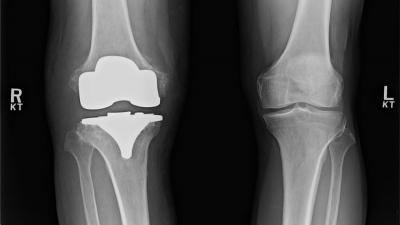

Διπλή χειρουργική επέμβαση για την αντιμετώπιση δύο σοβαρών παθήσεων με υψηλό επίπεδο επικινδυνότητας, πραγματοποιήθηκε με απόλυτη επιτυχία στο Metropolitan General.

Ασθενής, ηλικίας 70 ετών, με βεβαρημένο ιατρικό ιστορικό (καρκινοπαθής από επταετίας) και πολλαπλά παράλληλα σοβαρά προβλήματα υγείας, υποβλήθηκε πρώτα σε λαπαροσκοπική χολοκυστεκτομή και στην συνέχεια σε αντιμετώπιση ανευρύσματος κοιλιακής αορτής με τοποθέτηση ενδοαγγειακών μοσχευμάτων, στον ίδιο χειρουργικό χρόνο.

Karafoka.jpgΟι δύο επεμβάσεις διενεργήθηκαν από την επικεφαλής χειρουργό και συντονίστρια κ. Ελένη Καραφώκα-Μαύρου Γενική Χειρουργό, Διευθύντρια της Β' Κλινικής Ρομποτικής Χειρουργικής & Χειρουργικής Ογκολογίας του Metropolitan General και την ομάδα της, τον κ. Μάριο Παπαχρυσοστόμου, Επιμελητή Χειρουργικής και την κ. Μαρία Ψαρρού Αναισθησιολόγο, σε συνεργασία με τον υπεύθυνο της αγγειοχειρουργικής ομάδας, τον κ. Νικόλαο Πατέλη και τον συνεργάτη Αγγειοχειρουργό κ. Ιωάννη Τσάγκο. Η συγκεκριμένη διπλή χειρουργική  επέμβαση είχε μεγάλο βαθμό δυσκολίας και προσθετικό επίπεδο επικινδυνότητας. Για την πραγματοποίηση του εγχειρήματος επιστρατεύθηκε όλη η διαθέσιμη (και για τις δύο ειδικότητες) σύγχρονη βιοϊατρική τεχνολογία.